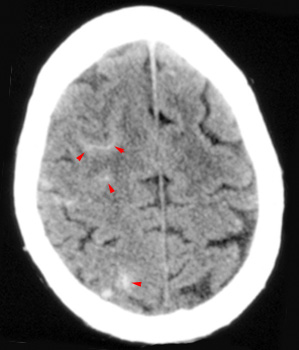

Head CT > Trauma > Subarachnoid Hemorrhage

Subarachnoid Hemorrhage

A subarachnoid hemorrhage occurs with injury of small arteries or veins on the surface of the brain. The ruptured vessel bleeds into the space between the pia and arachnoid matter. The most common cause of subarachnoid hemorrhage is trauma. In the absence of significant trauma, the most common cause of subarachnoid hemorrhage is the rupture of a cerebral aneurysm. When traumatic, subarachnoid hemorrhage occurs most commonly over the cerebral convexities or adjacent to otherwise injured brain (i.e. adjacent to a cerebral contusion). If there is a large amount of subarachnoid hemorrhage, particularly in the basilar cisterns, the physician should consider whether a ruptured aneurysm led to the subsequent trauma. Cerebral angiography may be needed for further evaluation. On CT, subarachnoid hemorrhage appears as focal high density in sulci and fissures or linear hyperdensity in the cerebral sulci. Again, the most common location of posttraumatic subarachnoid hemorrhage is over the cerebral convexity. This may be the only indication of cerebral injury.